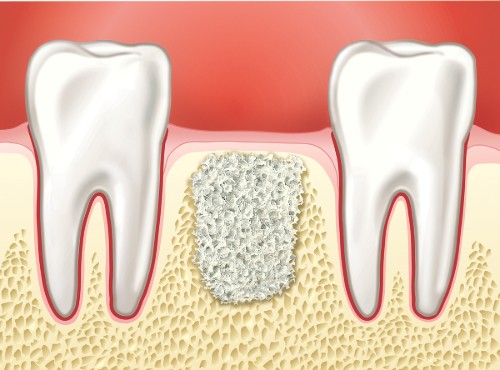

Missing teeth over a period of time can cause your jaw bone to atrophy, or resorb. This often results in poor quality and quantity of bone suitable for the placement of dental implants as well as long term shifting of remaining teeth and changes to facial structure. Most patients, in these situations, are not candidates for dental implants.

Fortunately, today we have the ability to grow bone where it is needed. This not only gives us the opportunity to place implants of proper length and width, but it also gives us a chance to restore functionality and aesthetic appearance.

Over a period of time, the jaw bone associated with missing teeth atrophies and is reabsorbed. This often leaves a condition in which there is poor quality and quantity of bone suitable for the placement of dental implants. In these situations, most patients are not candidates for the placement of dental implants.

With bone grafting we now have the opportunity to not only replace bone where it is missing, but we also have the ability to promote new bone growth in that location. This not only gives us the opportunity to place implants of proper length and width, it also gives us a chance to restore functionality and aesthetic appearance.

When an adult tooth is removed and not replaced, jaw bone deterioration may occur. Natural teeth are embedded in the jaw bone and stimulate the jaw bone through activities such as chewing and biting. When teeth are missing, the alveolar bone, or the portion of the jaw bone that anchors the teeth in the mouth, no longer receives the necessary stimulation and begins to break down, or resorb. The body no longer uses or “needs” the jaw bone, so it deteriorates and goes away.